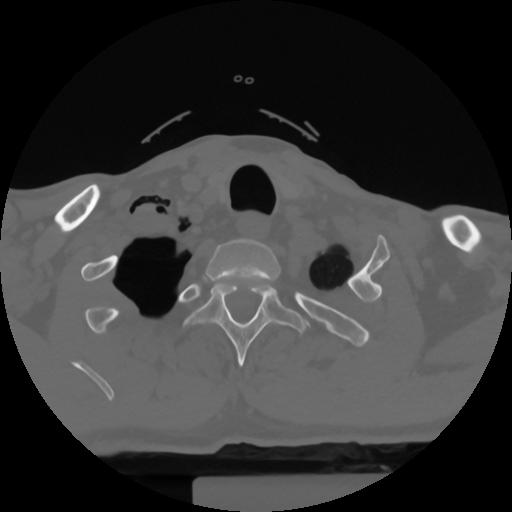

12 P.BLANDAS,,Vol,0.5,P.BLANDAS,,